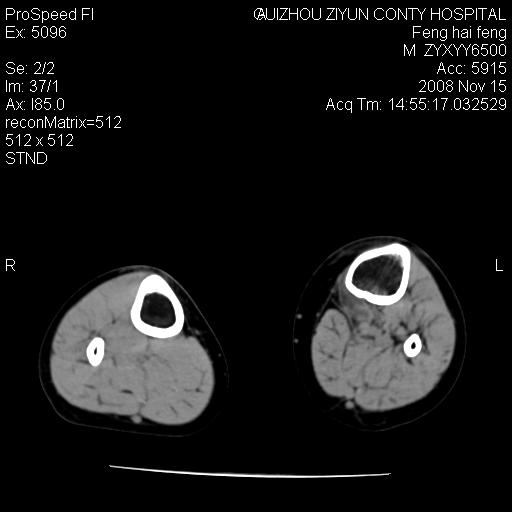

标题: CT16656:M 14Y 左膝关节肿胀一年余。其余病史不详。 [打印本页]

标题: CT16656:M 14Y 左膝关节肿胀一年余。其余病史不详。

考虑左侧髌骨结核;左膝关节滑膜肿胀、增厚,关节囊积液。

左膝滑膜型关节结核可能性大!支持!滑膜型关节结核主要ct表现:关节囊肿胀,积液,关节面见小破坏灶,并见点状死骨!

好大的左腿!考虑左侧髌骨结核,左膝关节滑膜肿胀、增厚,关节囊积液。

左侧髌骨结核;左膝关节滑膜肿胀、增厚,关节囊积液